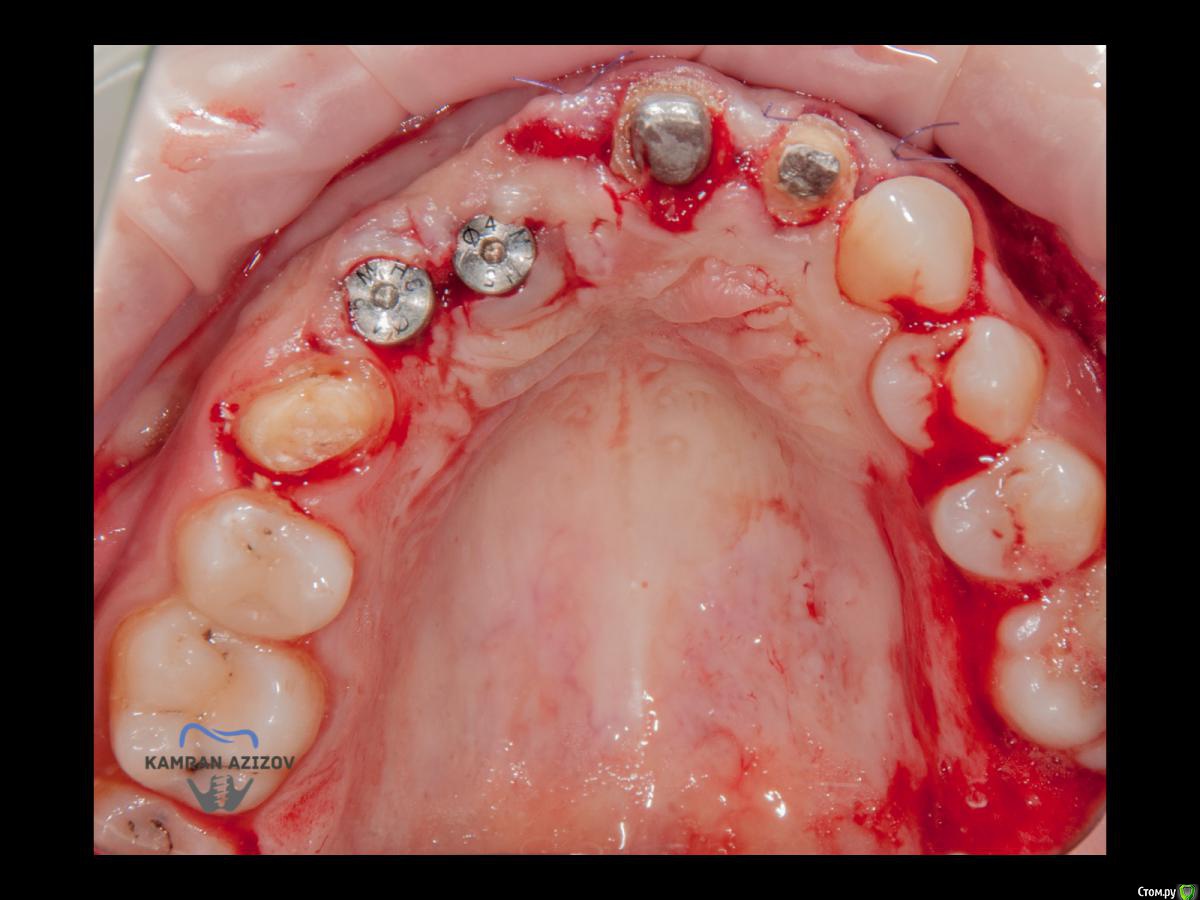

kamranchick Опубликовано 6 апреля, 2019 Поделиться Опубликовано 6 апреля, 2019 (изменено) Хай Гайсдавно ничего не комментировал и не выкладывал, что то настроения не было, да и муза не посещалаСитуация следующаяпришла пациентка, жалобы на неприятный запах из рта, сначала не понял что за хрень, ну как распилил мост понял че к чему... халтура.Ну и по кейсуУдаление клыка и 2ки, через 2 месяца навигация, имплантация + Шашлыки по карлоссу, смена формиков, временное протезирование. только мягкие ткани, Изменено 6 апреля, 2019 пользователем kamranchick 7 1 Ссылка на комментарий